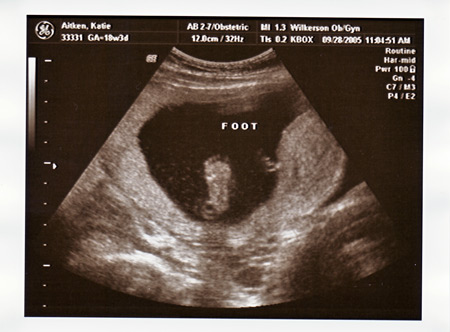

I had my ultrasound today, and found out everything is perfect and in place. We are so excited that Maeve will have a little sister to play with!!!